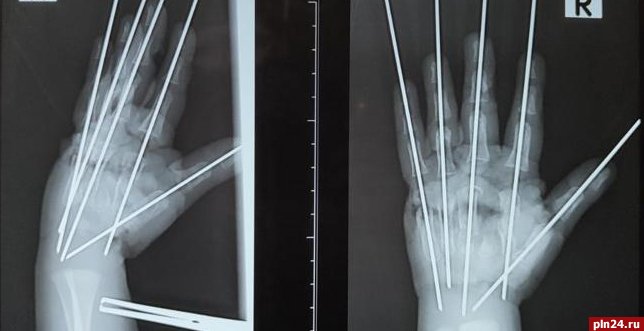

Фото: пресс-служба Педиатрического университета

«Травма очень тяжёлая, что обусловлено раздавливающим механизмом мясорубки. Повреждена была вся кисть, раздроблены кости, сухожилия, сосуды, нервы. Фактически имела место ампутация – кисть держалась на нескольких связках. Нашей задачей было сохранить жизнеспособные ткани, восстановить анатомию конечности и кровообращение»,  –  сообщил врач.

Как отметили в медучреждении, в  ходе операции специалисты Педиатрического университета собрали по частям травмированную руку мальчика.

«Мы выполнили металлоостеозинтез, чтобы соединить осколки костей. Затем было необходимо восстановить кровоснабжение кисти»,  – рассказал Антон Волков.

Ребёнку потребовалась аутовенозная пластика: размозженный участок  локтевой артерии хирурги заместили фрагментом подкожной вены пациента. Медики отметили, что после этого пальцы ребёнка стали понемногу розоветь.